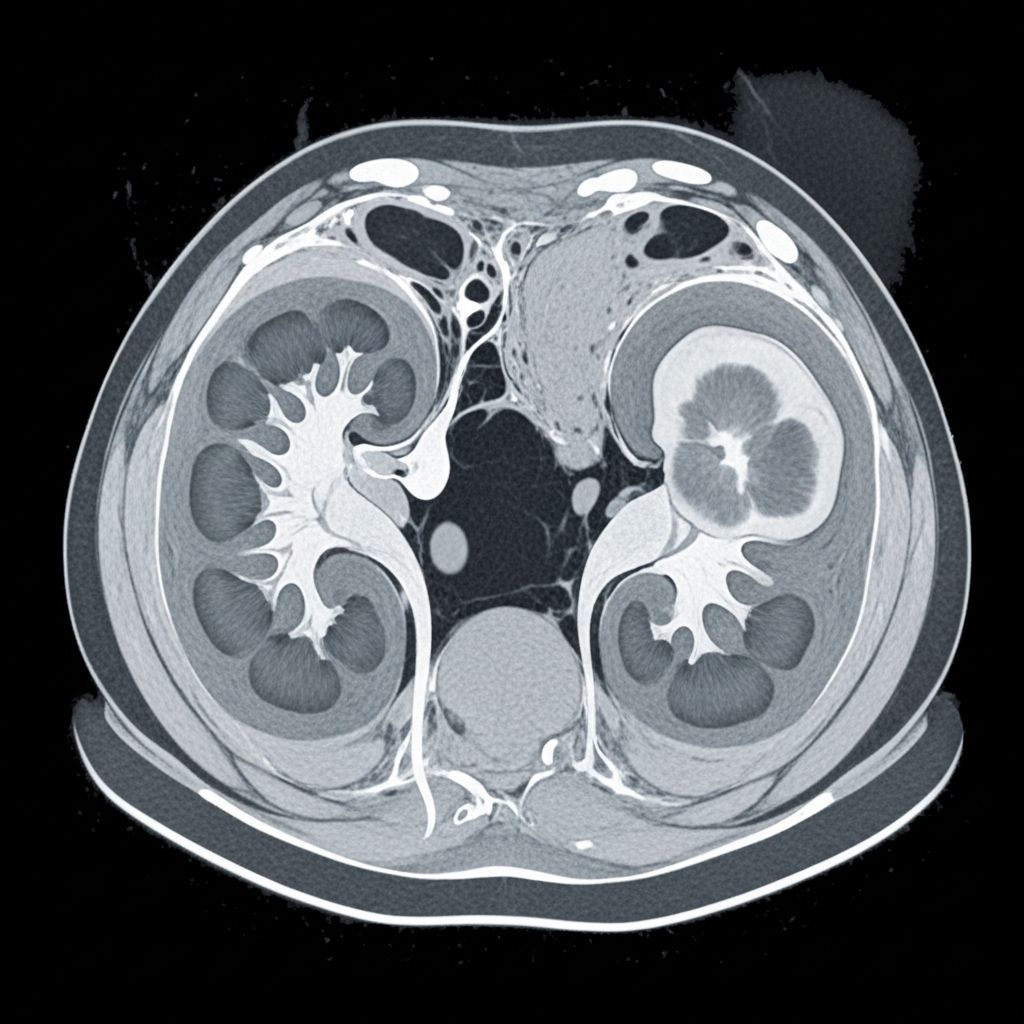

How a CT Scan Detects Kidney Cancer

A CT scan uses narrow beams of X-rays to create cross-sectional images of the body, which are processed by a computer to form clear, two-dimensional or three-dimensional pictures of the internal organs. These images provide detailed information about the location, size, and shape of any tumors in the kidneys.

- Show the exact location of a tumor

- Provide details on tumor shape and size

- Detect whether cancer has spread to lymph nodes or other organs

- Find incidental tumors during scans ordered for unrelated reasons

CT scans are among the most sensitive and specific methods for identifying kidney tumors. According to recent studies, CT scans are over 99% accurate in detecting kidney cancer. They are especially effective in revealing tumors’ size and whether cancer has spread beyond the kidney to adjacent lymph nodes or other organs.